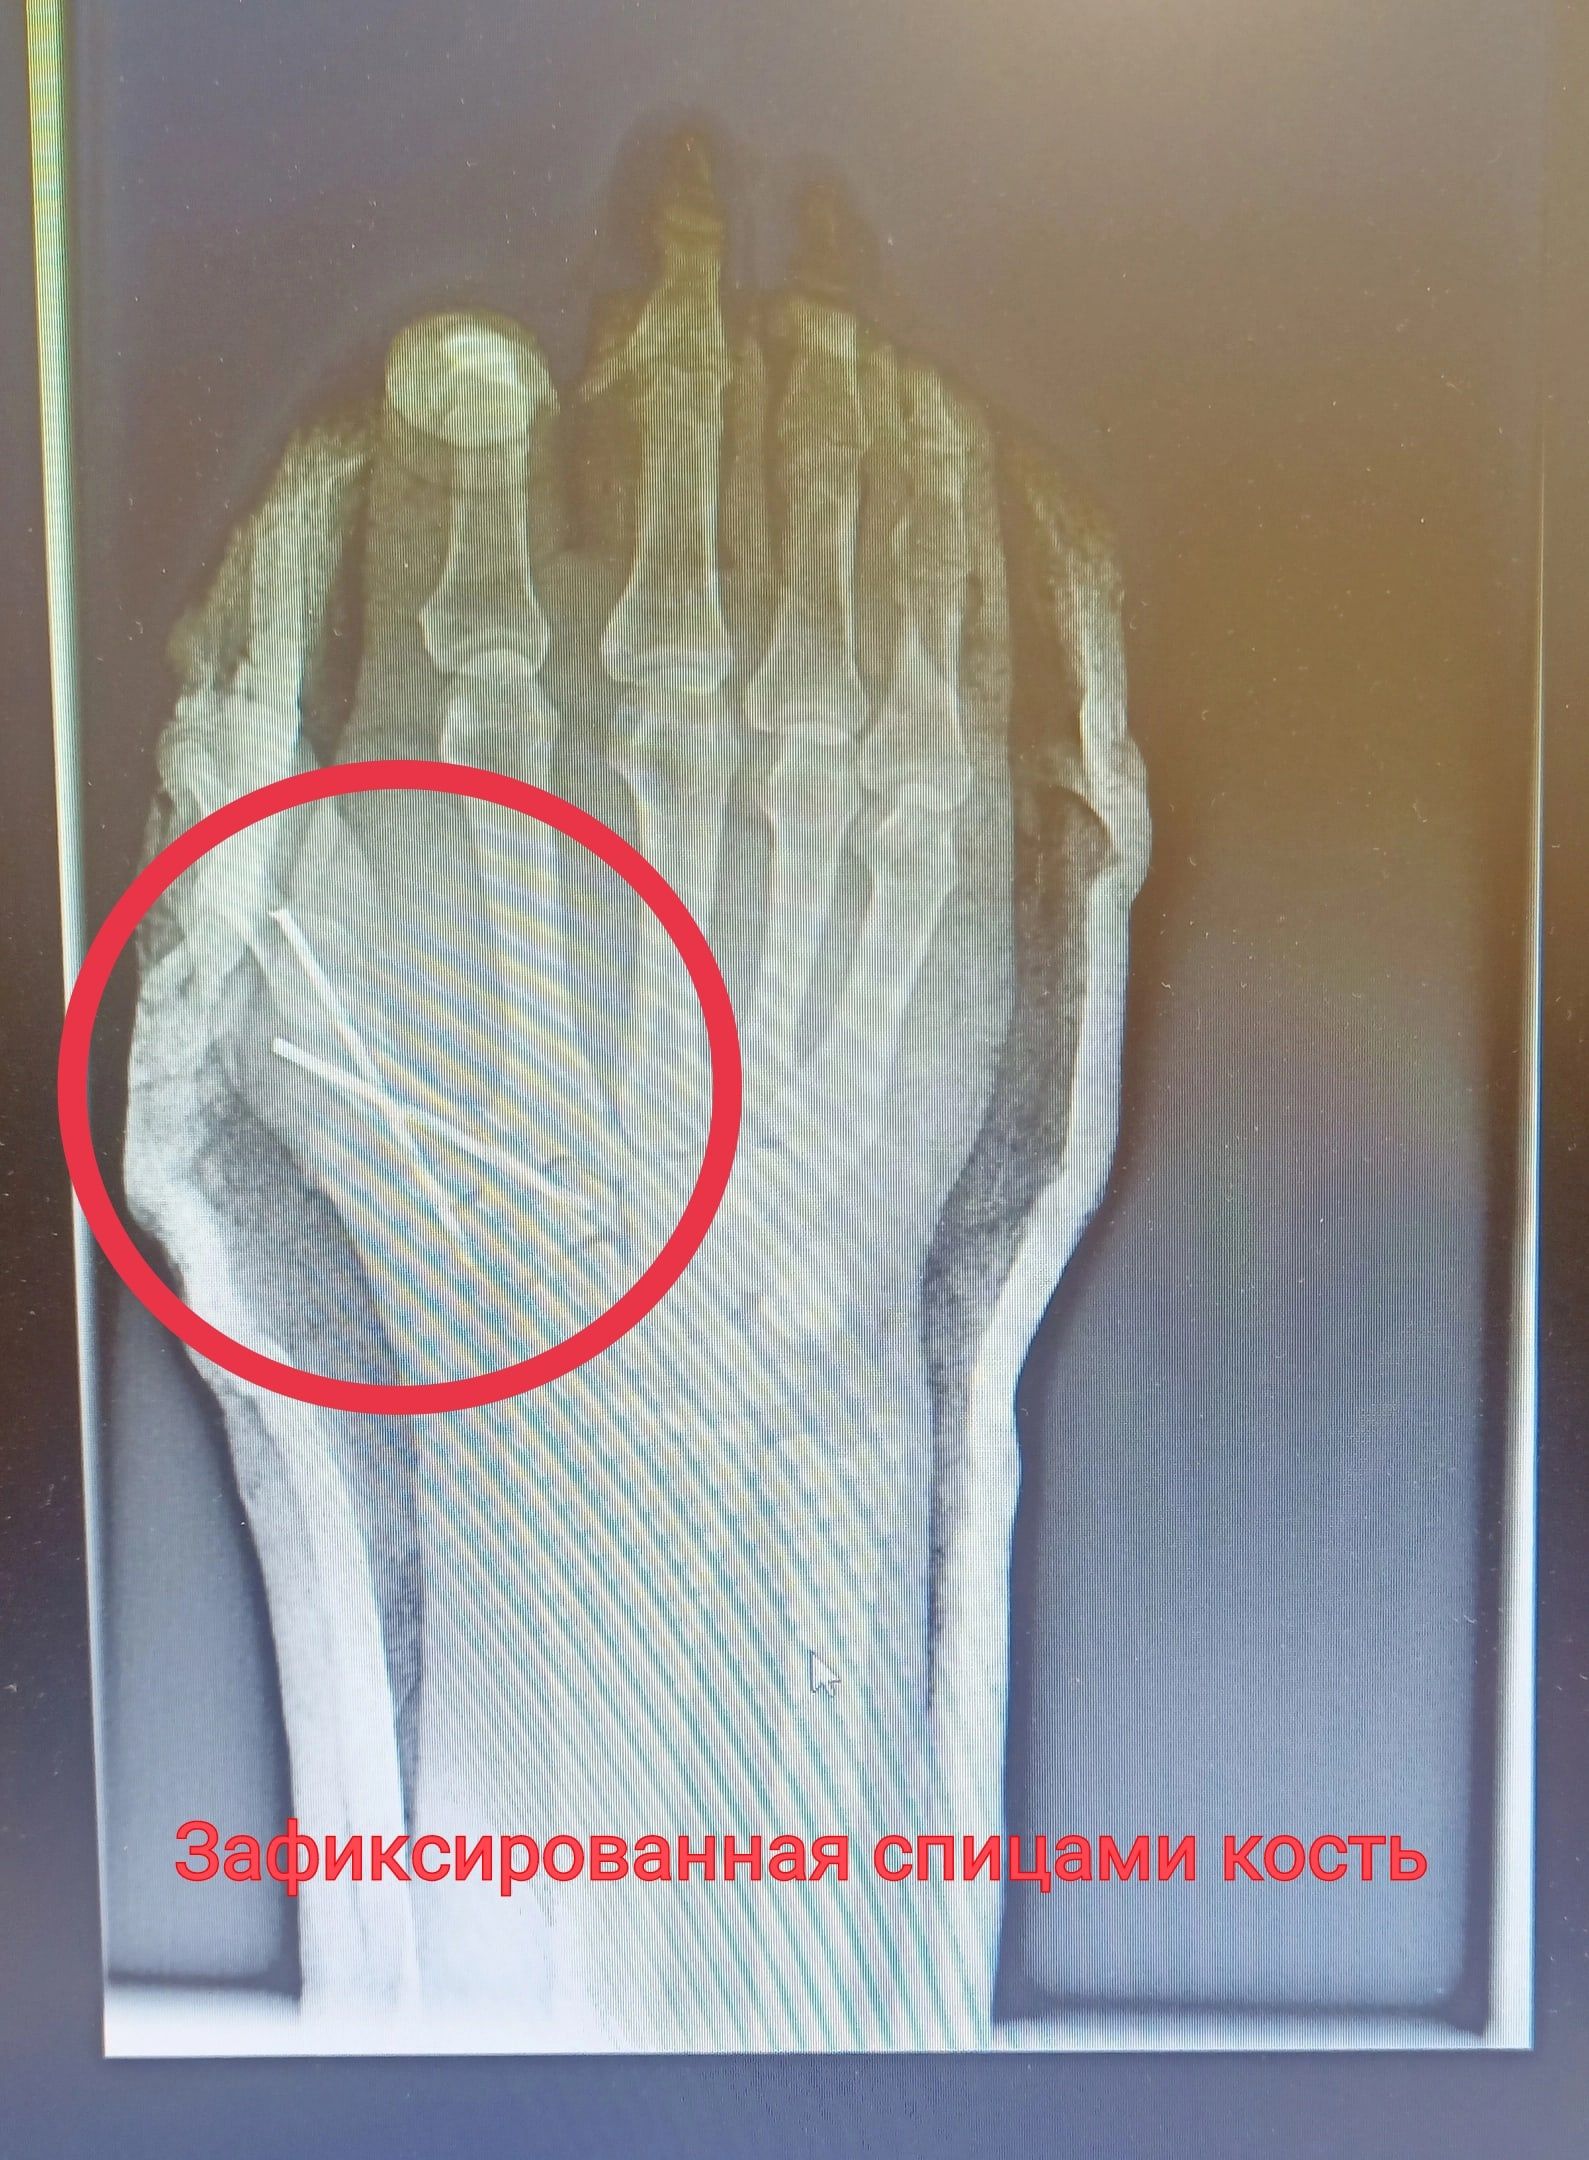

Травма оказалась сложной, мужчина мог лишиться большого пальца, ведь он почти полностью был отрезан от руки. Врач восстановил сначала пястную кость, зафиксировав ее спицами, потом сухожилия. Операция длилась 2,5 часа.